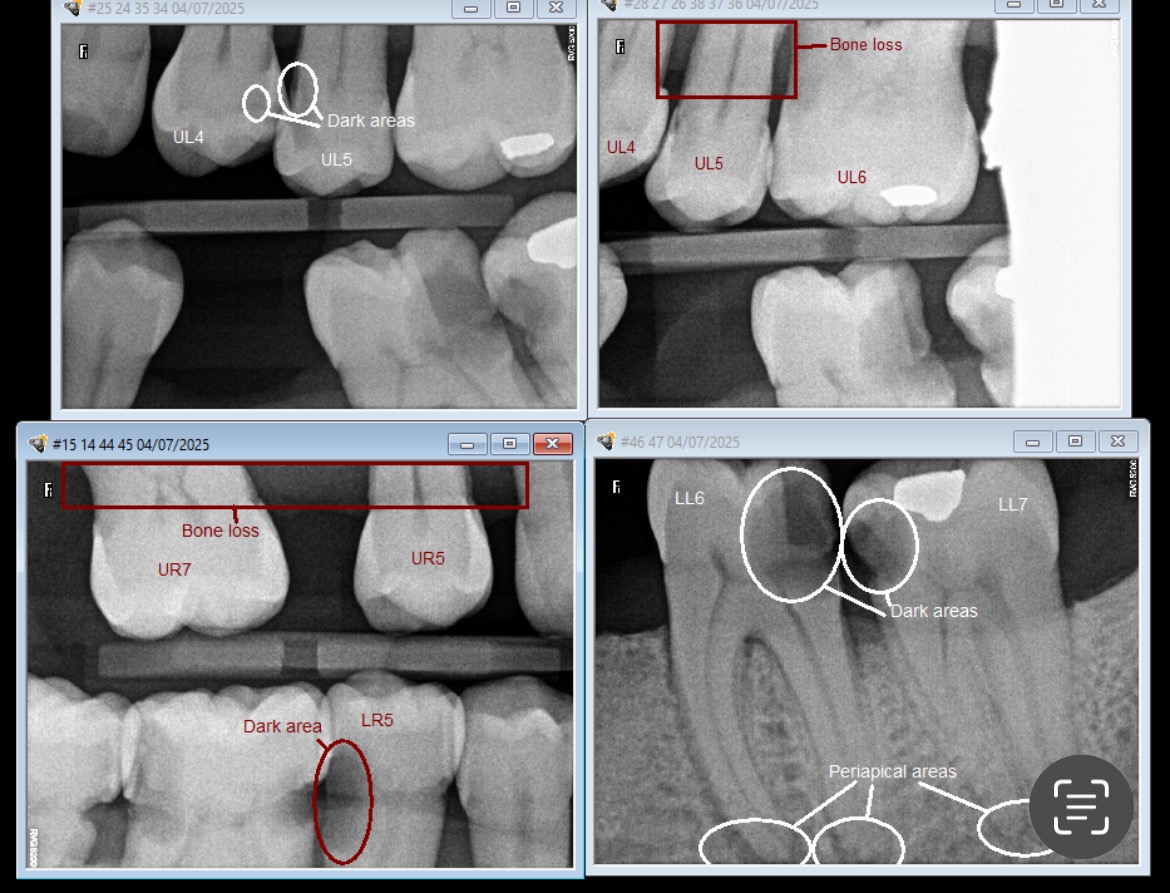

For the past year, Bluebelle has been suffering with serious dental problems that have left her in constant pain. Eating, sleeping, and even speaking has become difficult – let alone singing. She’s now at a critical point where major dental surgery is the only option left to relieve the pain and give her a chance to get back to doing what she loves most: making music.

We’ve explored every possible route through the NHS and community dentistry, but the severity of the work she needs – including surgical extractions, reconstruction, and implants – is not accessible without going private. The total cost is £12,000, and we simply can’t cover this alone.

• Full dental assessment and scans